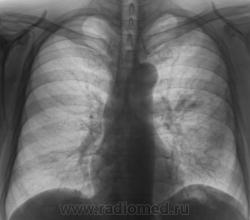

tbc

А, какой ТВС?